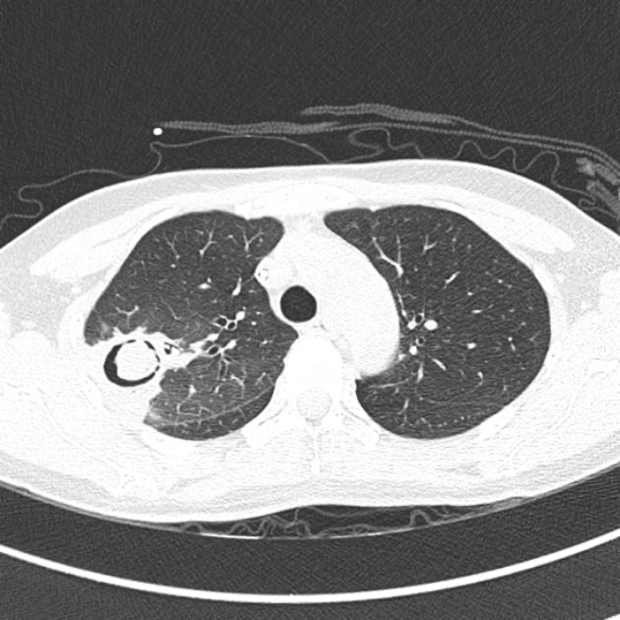

A radiographic sign of a mobile intracavitary fungus ball surrounded by air, classically seen in aspergillosis

What is Monod sign?